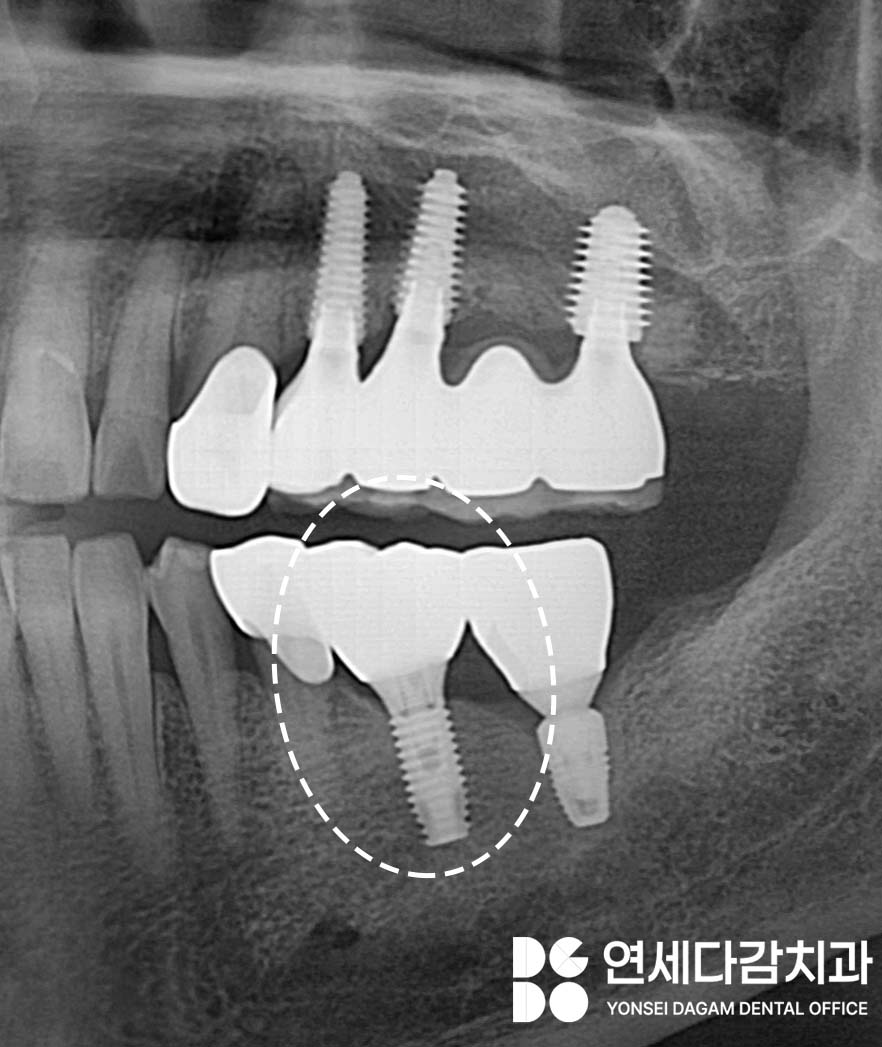

개롱역 치과 에서 예를 들자면

치아 사이 보철물이 파절되어

이 사이에 긴밀함이 느슨해진 경우가 있습니다.

이럴 땐 식편압입(음식물이 끼는 현상)이

생기게 됩니다.

치료받은 지 오래되었기에

새롭게 다시 식립 해야 된다고

생각하실 수 있으나,

치관 부위인

상부 보철만 다시 제작하여

해결할 수 있습니다.

그러기 위해서는 고정체의

형태를 자세히 분석해야 됩니다.

엑스레이 상 두 개의

종류가 다른 것을 알 수 있습니다.